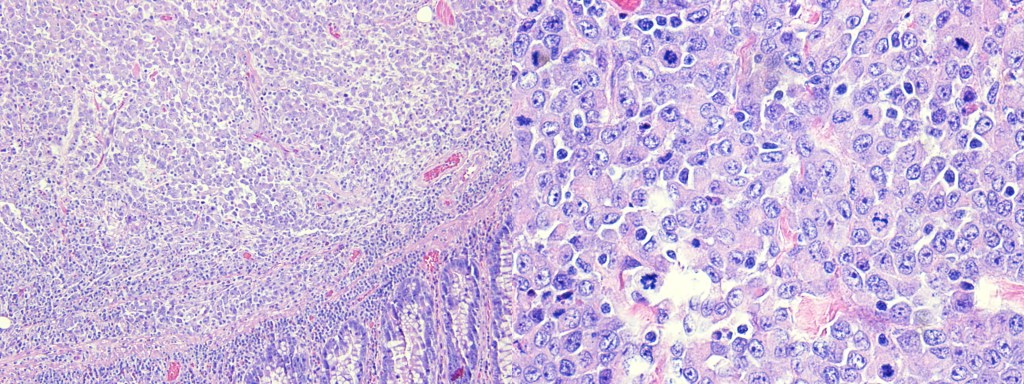

Image 1. Hematoxylin and Eosin-stained composite image of Medullary Colon Cancer. Left side (4x magnification) shows colonic mucosa with a well-demarcated solid nest of tumor cells with conspicuous lymphoplasmacytic infiltrates. Right side (20x magnification) shows a higher magnification of the pleomorphic tumor cells with irregular nuclear membranes, vesicular chromatin, prominent nucleoli and multiple mitotic figures. Medullary colon cancers are usually right-sided and have a better prognosis compared with poorly-differentiated or undifferentiated adenocarcinoma of the colon.6